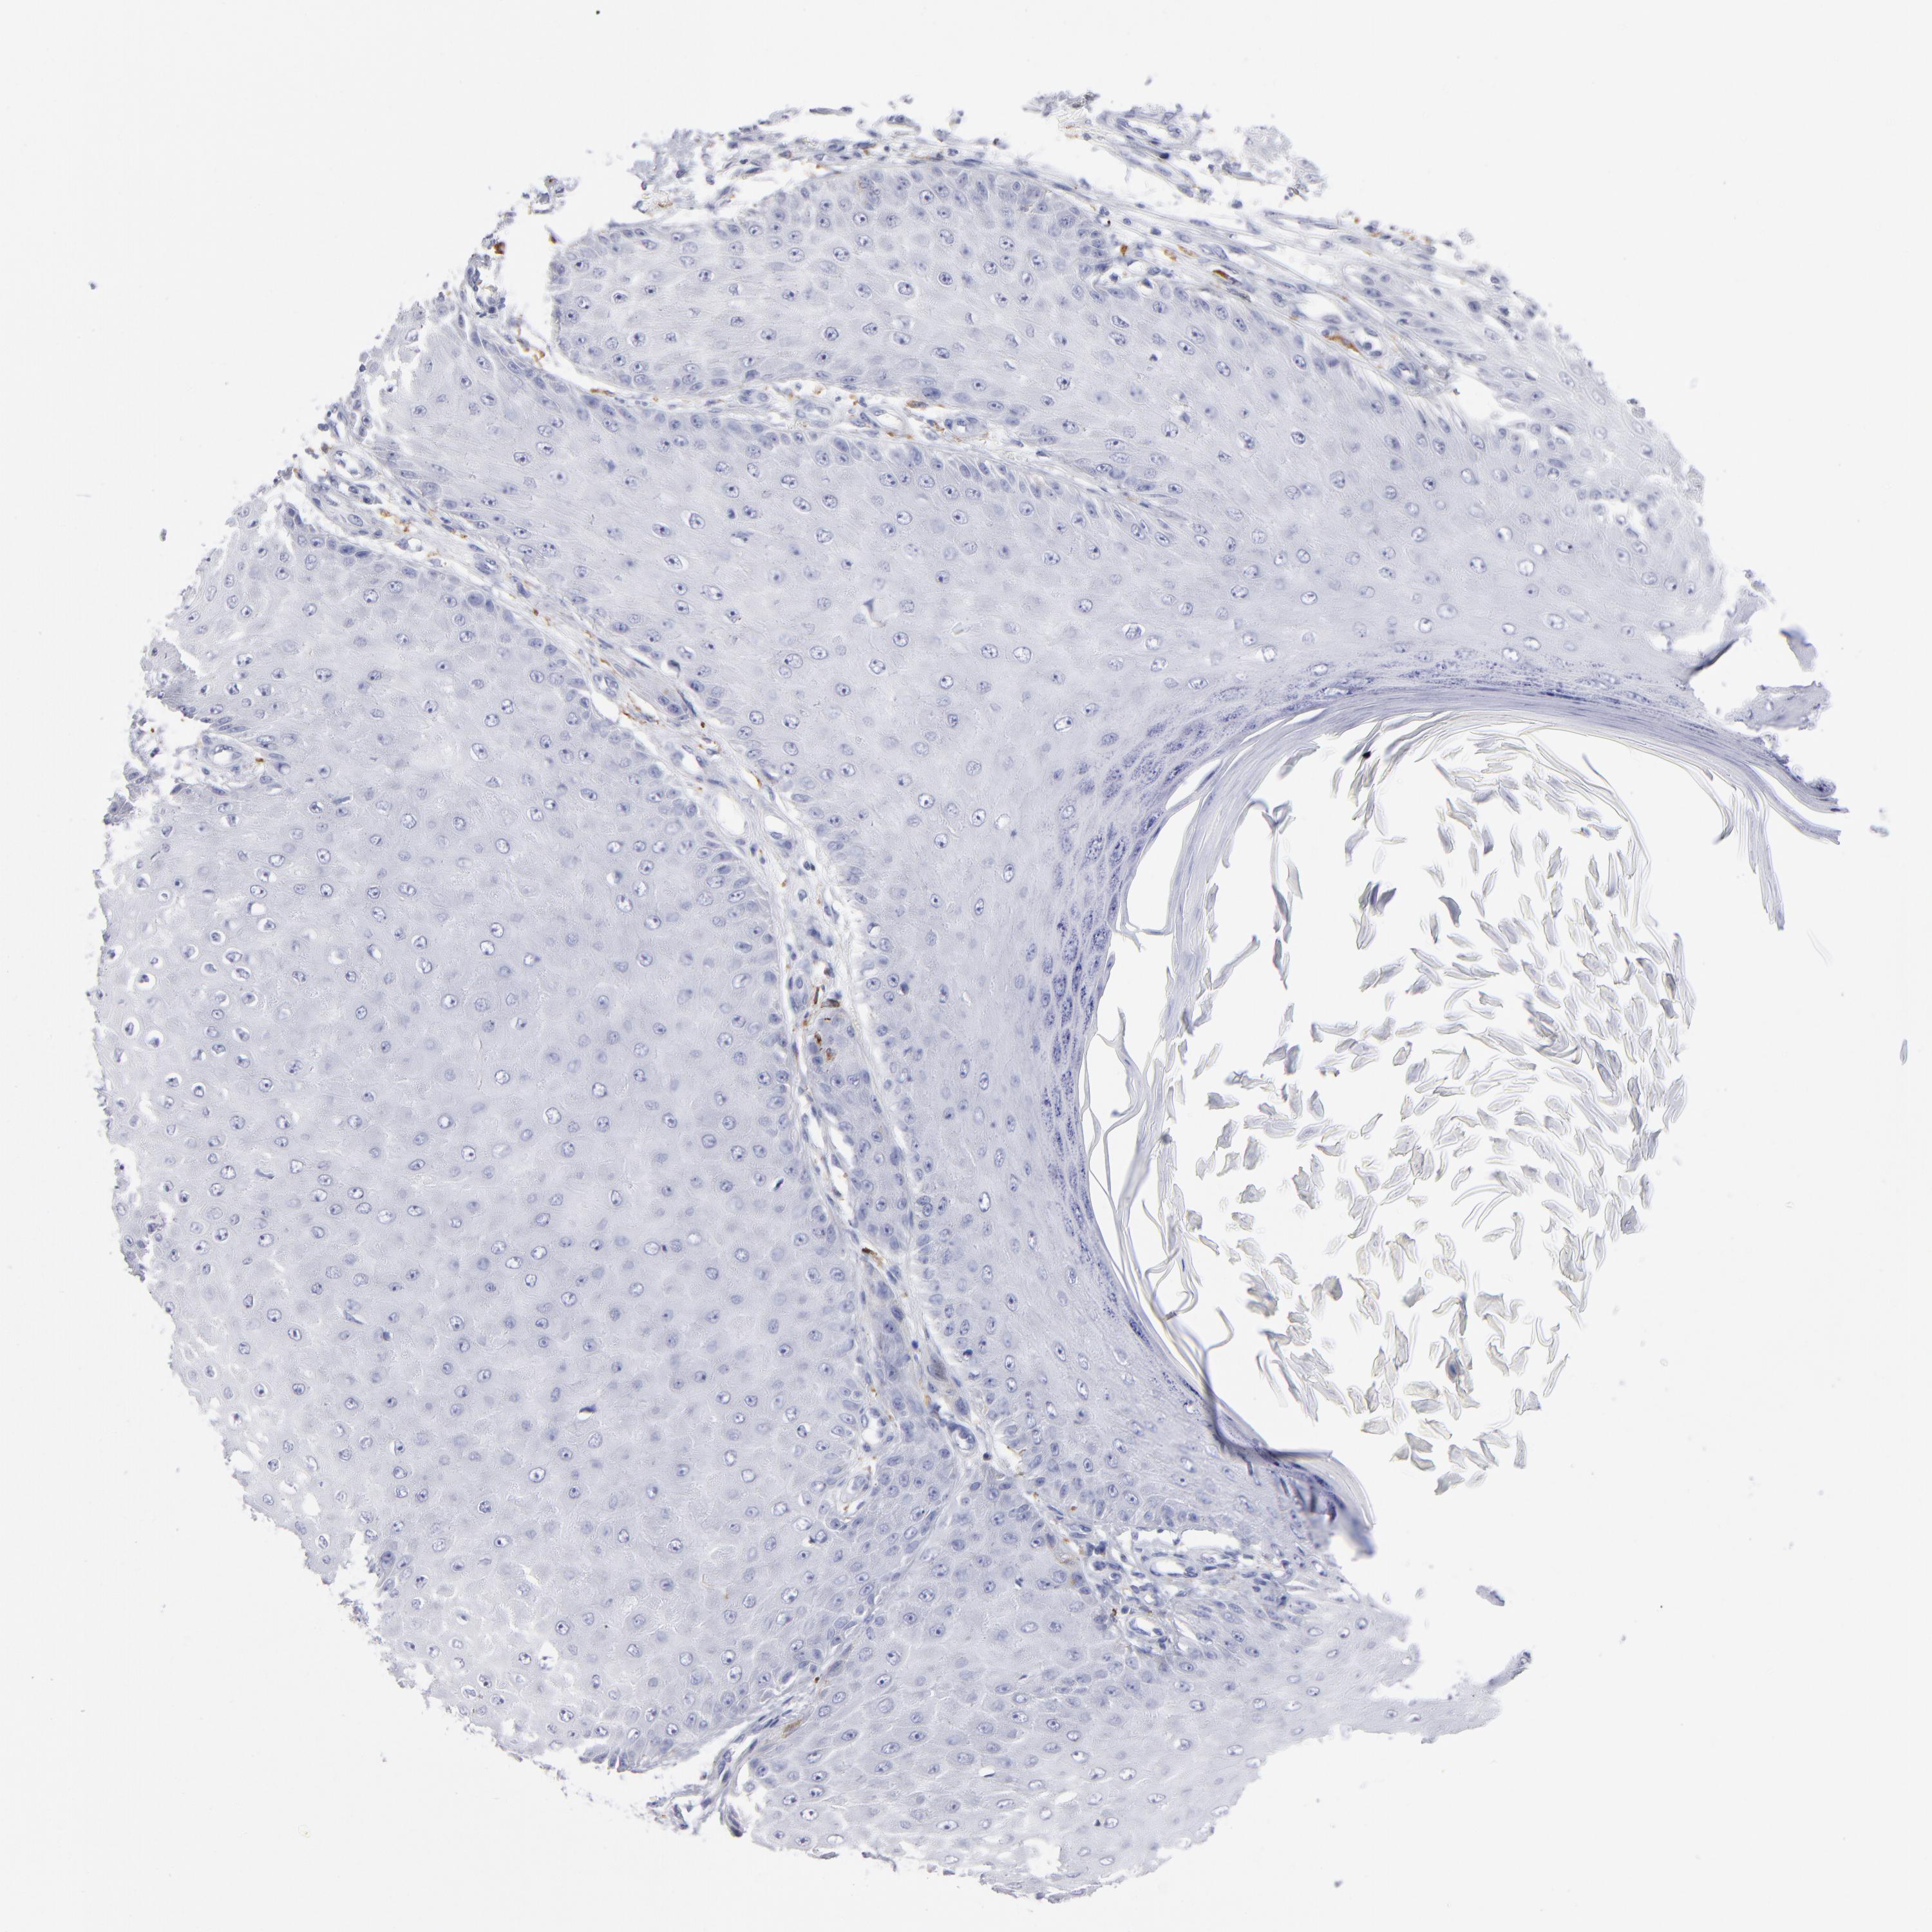

SKIN CANCER - Protein expressioni

A mouse-over function shows sample information and annotation data. Click on an image to view it in a full screen mode. Samples can be filtered based on level of antibody staining by selecting one or several of the following categories: high, medium, low and not detected. The assay and annotation is described here.

Antibody stainingi

Antibody staining in the annotated cell types in the current human tissue is reported as not detected, low, medium, or high, based on conventional immunohistochemistry profiling in selected tissues. This score is based on the combination of the staining intensity and fraction of stained cells.

Each image is clickable and will lead to virtual microscopy that enables deeper exploration of all samples and also displays staining intensity scores, fraction scores and subcellular localization as well as patient and tissue information for each sample.

Antibody HPA003740

Basal cell carcinoma